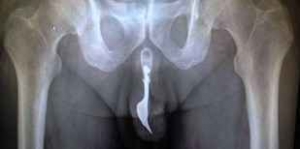

【引用】imgassets.com